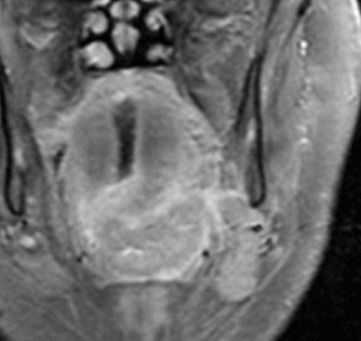

МРТ мягких тканей шеи с контрастированием. Распространения рака ротоглотки на парафарингеальное пространство.

Плоскоклеточный рак основания языка также может прорасти в соседние глубокие пространства. Встречается периневральное распространение. Кроме того, следует определить линии пересечения опухоли, как это имеет значения для выбор объема операции. Плоскоклеточный рак основания языка имеет склонность вторгаться книзу в подчелюстное пространство и спускаться вплоть до надгортанника. Кроме того, при МРТ мягких тканей следует оценить инвазию нижней челюсти.

МРТ мягких тканей шеи с контрастированием. Распространение рака ротоглотки на подчелюстное пространство.